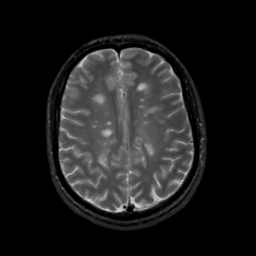

MR Study #3, February 24, 1991 -- Slice #34

[Home][Help][Clinical][Tour 1][Tour 2] Slice 34